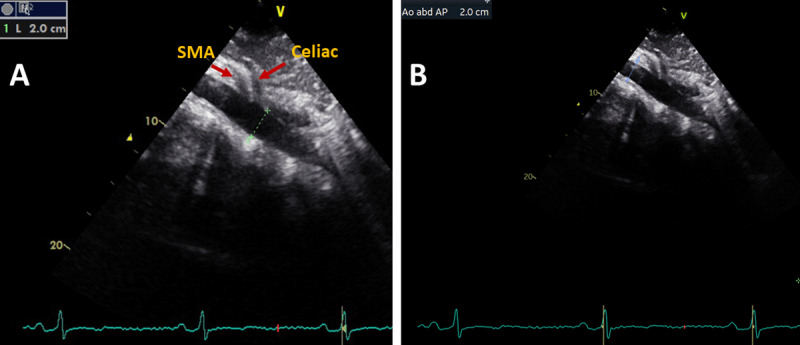

Methods: In 2022, a total of 189 patients with cardiac symptoms visiting the Mnazi Mmoja Referral Hospital (MMH) in Zanzibar underwent standard transthoracic echocardiography (TTE). Demographics and clinical data were recorded. AA diameter was routinely assessed in 137 patients. AA was measured by the leading-edge-to-leading-edge method from a longitudinal plane, and AAA was defined as an AA diameter of ≥3.0 cm. SPSS version 29.0 was used for data analysis. The prevalence of AAA was estimated as the number of AAA cases divided by the number of all screened subjects. Correlates of AA diameter were tested in univariate and multivariate linear regression analyses.

Results: AA could be visualized in 128 (93.4%) patients (43% of men and 57% of women). The mean age was 54.4 ± 15.9 years. The mean AA diameter was 2.1 ± 0.3 cm in the entire study population and was significantly greater in men than women (2.2 ± 0.3 vs 2.1 ± 0.3 cm, p = 0.005) and in individuals aged ≥60 years than those aged <60 years (2.3 ± 0.3 vs 2.1 ± 0.3 cm, p = 0.003). The prevalence of AAA was 1.6%. In a multivariate linear regression analysis, higher age, male gender, atrial fibrillation and left ventricular (LV) mass were independent correlates of greater AA diameter, adjusted for clinic systolic blood pressure, ascending aortic diameter and LV ejection fraction (multiple R2 = 0.38, p < 0.001).